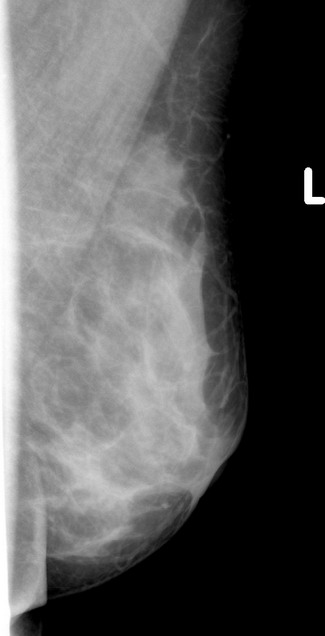

标题: x2364:女,45岁,乳房胀痛,触及硬块求诊 [打印本页]

女,45岁,乳房胀痛,触及硬块求诊

体查:左侧乳房可触及多个硬块,活动度可,无压痛

本人对于乳腺在太多的拿不准,发现乳腺太难看了,我的意见是:

1,左侧乳腺外上象限肿块样影,腺体增生?乳腺纤维瘤?

2,右乳外下象限局部密度增高明显,建议必要时彩超检查除外其他。

3,双侧乳腺小叶增生。

乳头稍凹陷,乳晕皮肤增厚,乳腺非对称性致密,未见明显肿块影,未见异常粗大血管和淋巴结

考虑双侧乳腺小叶增生症.

乳腺非对称性致密,未见明显肿块影,未见异常粗大血管和淋巴结